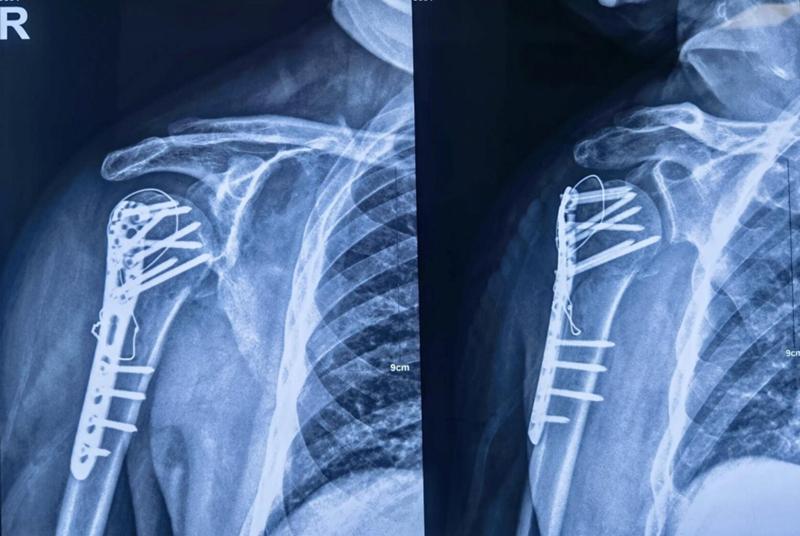

Xxx,男,65岁,右肱骨近端四部分骨折一周。

图16 术前X片

肩前外侧劈三角肌入路,三角肌前束和中间束肌肉间隙进入,双套固定技术加强固定。

图19 术后X片